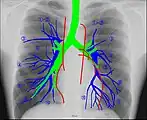

Human chest radiographic anatomy.

Radioanatomy (x-ray anatomy) is an anatomy discipline that involves studying anatomy through the use of radiographic films.[3] The x-ray film represents a two-dimensional image of a three-dimensional object due to the summary projection of different anatomical structures onto a planar surface.